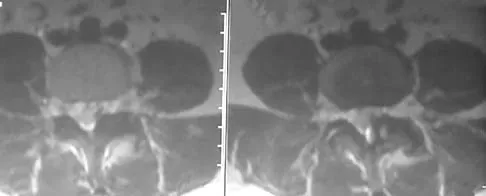

A 55-year-old woman with a long history of low back and left lower extremity pain has failed to respond to exhaustive nonsurgical management. MRI scans show bulging and degeneration at L3-4 and L4-5 as well as a normal disk at L2-3 and L5-S1. She undergoes provocative lumbar diskography at L3-4, L4-5, and L5-S1. Post-diskography axial CT images of L3-4 and L4-5 are shown in Figures 6a and 6b, respectively. The injections at L3-4 and L4-5 produce no pain. The injection at L5-S1 produces 10/10 concordant back pain with radiation to the lower extremity. What is the most appropriate recommendation at this time?

Explanation